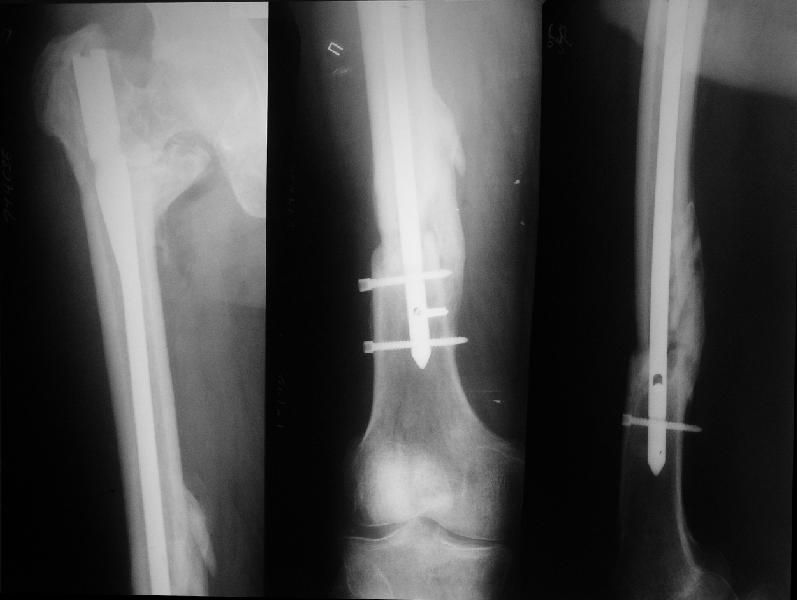

На прошлой неделе оперировали похожего пациента. 2 года после неудачного остеосинтеза PFN в другом регионе. После удаления остатков железа выявилось несращение вертельной области.

Поскольку в нашем случае выявилась подвижность, мы наложили дистрактор таз-бедро на 3 дня, и сделали остеосинтез гаммой без остеотомии. То, что произошла "корригирующая остеоклазия" в подвертельной области, выявили после введения гвоздя. Пациент уже уехал домой, будем наблюдать.